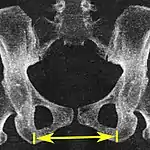

| Pelvic inlet | Transverse diameter of the pelvic inlet | ![]()  |

![]() Coronal plane  |

The iliopectineal lines, at widest transverse distance. | 13 to 14.5 cm.[4] |